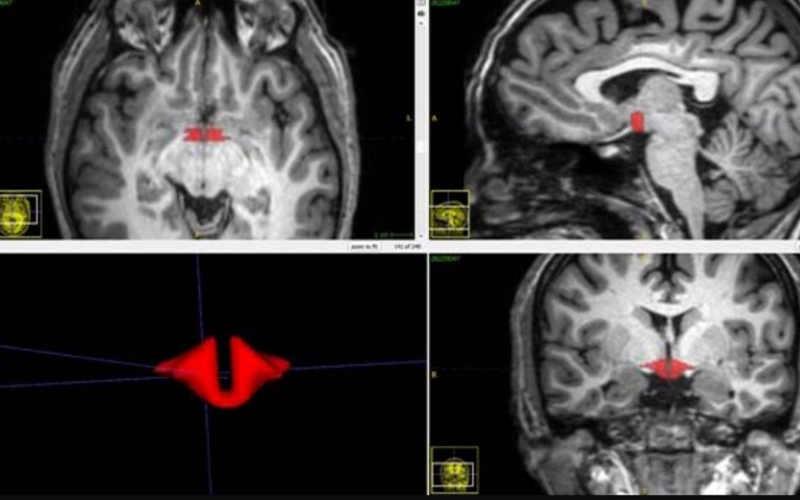

Studiu controversat: femeile care iau contraceptive au o parte a creierului mai mică